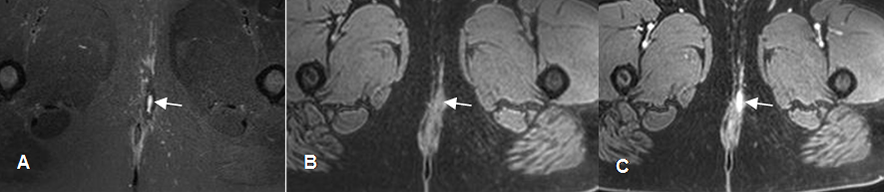

Fig 66. Fístula.

A: RM axial en STIR. Fístula perianal izquierda.

B: Thriveax T1 simple y C: Thriveax T1 con contraste. El trayecto fistuloso realza con el contraste.